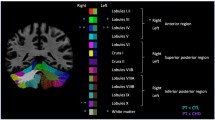

A total of 24 preterm infants with punctate CBH were included and each matched to two preterm control infants. T1-, T2-weighted images and diffusion-weighted imaging were acquired on a 3T magnetic resonance imaging (MRI) system. Regions of interest were drawn on a population-specific neonatal template and automatically registered to individual fractional anisotropy (FA) maps. Brain volumes were automatically computed. Neurodevelopmental outcome was assessed using the Bayley scales of Infant and Toddler Development at 2 years of corrected age.

CBHs were not significantly related to FA in the posterior limb of the internal capsule and corpus callosum or to cerebellar volume. Infants with CBH did not have poorer neurodevelopmental outcome compared with control infants.